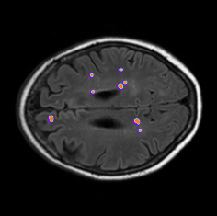

Recent years have witnessed a substantial growth in the number of deep learning methods for medical image segmentation [1, 2, 3, 4]. Widely used loss functions for segmentation, e.g., Dice or cross-entropy, are based on regional integrals, which are convenient for training deep neural networks. In practice, these regional integrals are summations over the segmentation regions of differentiable functions, each directly invoking the softmax probability outputs of the network. Therefore, standard stochastic optimizers such as SGD are directly applicable. Unfortunately, difficulties occur for highly unbalanced segmentations, for instance, when the size of target foreground region is several orders of magnitude less than the background size. For example, in the characterization of white matter hyperintensities (WMH) of presumed vascular origin, the foreground composed of WMH regions may be 500 times smaller than the background (see the typical example in Fig. 1). In such cases, quite common in medical image analysis, standard regional losses contain foreground and background terms with values that differ considerably, typically by several orders of magnitude, potentially affecting performance and training stability [5, 6].